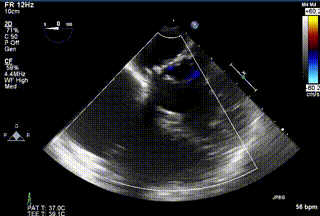

2021年12月24日,復(fù)旦大學(xué)附屬中山醫(yī)院葛均波院士團隊成功應(yīng)用LuX-Valve Plus為一例極重度三尖瓣反流(TR)合并房顫、房缺的患者完成了經(jīng)血管三尖瓣置換術(shù),這是在前基礎(chǔ)上,本周完成的第三例經(jīng)血管三尖瓣置換手術(shù),葛均波院士、周達(dá)新教授等與心外科魏來教授、賴顥教授,心超室的潘翠珍教授、李偉教授及麻醉科的郭克芳教授共同完成了本周手術(shù),均獲得圓滿成功!患者術(shù)后超聲顯示無TR,臨床癥狀明顯改善。本周手術(shù)的成功也為LuX-Valve Plus救治性臨床研究添上了濃墨重彩的一筆。

三例患者入院后,葛均波院士團隊周達(dá)新教授、潘文志教授、張源博士、陳莎莎博士及心超室的潘翠珍教授、李偉教授對患者的情況進行詳細(xì)評估和討論,最終決定為三例患者選擇LuX-Valve Plus40mm、50mm和50mm型號的瓣膜進行手術(shù)治療。手術(shù)后即刻拔除氣管插管,術(shù)后患者三尖瓣反流癥狀得到顯著改善,復(fù)查心超結(jié)果顯示人工三尖瓣瓣膜支架固定穩(wěn)定,瓣葉關(guān)閉形態(tài)未見異常,未見明顯反流。